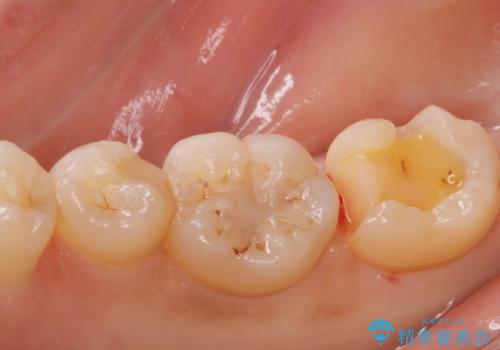

歯に食べ物が詰まる。

- 歯に食べ物が詰まるとの事で来院。

虫歯により歯が欠けていたので拡大鏡下で虫歯を除去した後、セラミックの詰め物で治療しました。

適合の良い詰め物が入りました。

セラミックスは虫歯の再発のリスクが低くなります。